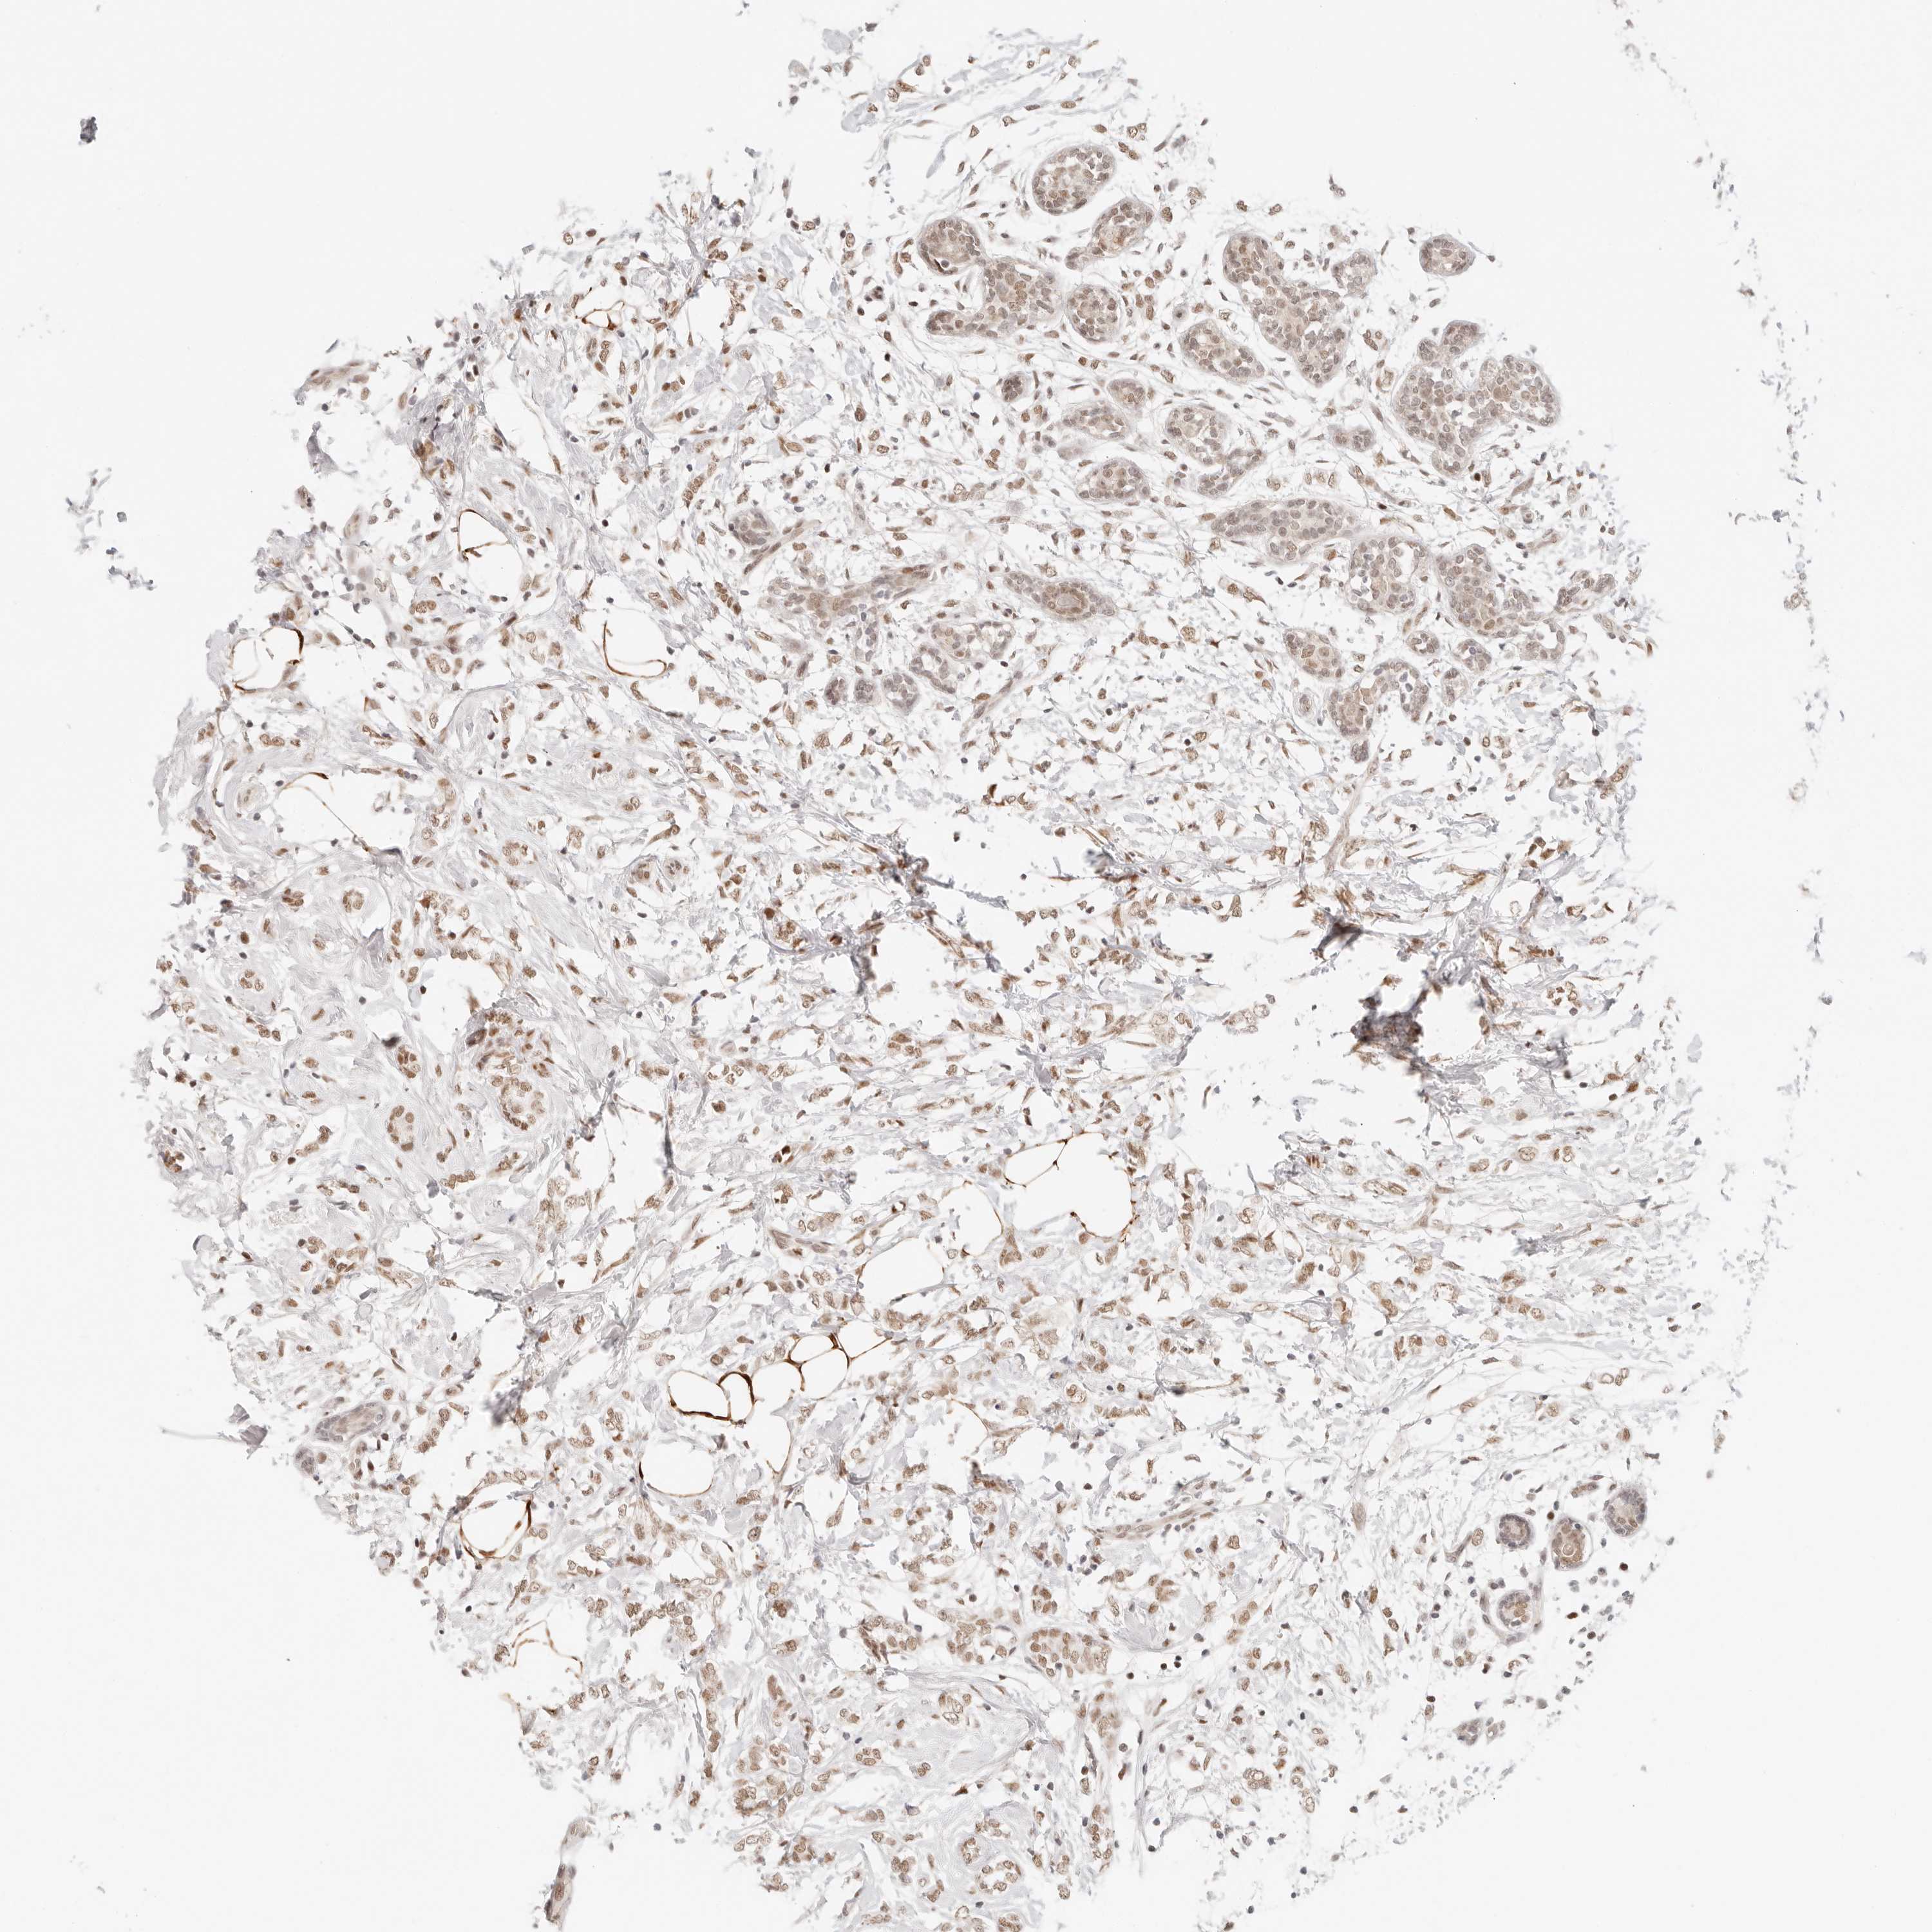

BRCA TCGA BRCA VALIDATION PROTEIN EXPRESSION

Breast cancer

Human cancer

Breast invasive carcinoma